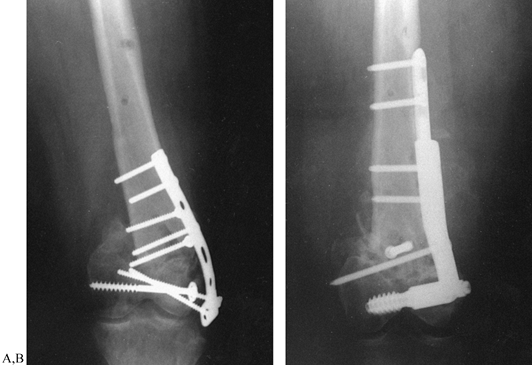

Figure 30.4. A:

AP radiograph of a 24-year-old woman 18 months after a T-type

supracondylar fracture of the femur treated with an AO T plate. She has

a painful nonunion with shortening and a varus deformity. B: AP radiograph of treatment with an Alta distal 95° condylar plate and screw combined with autologous bone graft.

Figure 30.5. Supracondylar femoral nonunion. A: AP radiograph of the femur in a 35-year-old man who sustained a grade 3A open comminuted supracondylar fracture. B:

After irrigation, debridement, and plate fixation, the fracture became

infected and went on to a nonunion. This AP radiograph shows the

original internal fixation with antibiotic beads in place. C,D:

The plate and screws were removed and after resolution of the

infection, the original treating physician internally fixed the

fracture with a retrograde supracondylar nail. Unfortunately, this

failed as well, resulting in a persistent nonunion. E,F:

I first encountered the patient 18 months after the original fracture.

There had been no evidence of infection for 15 months. I removed the

nail and screws, and through an anterolateral approach applied an Alta

lateral plate assembly. I augmented this with a smaller anterior plate

and applied an iliac crest bone graft. The nonunion healed in 16 weeks

with no recurrence of infection. Knee motion was from full extension to

110° of flexion. -